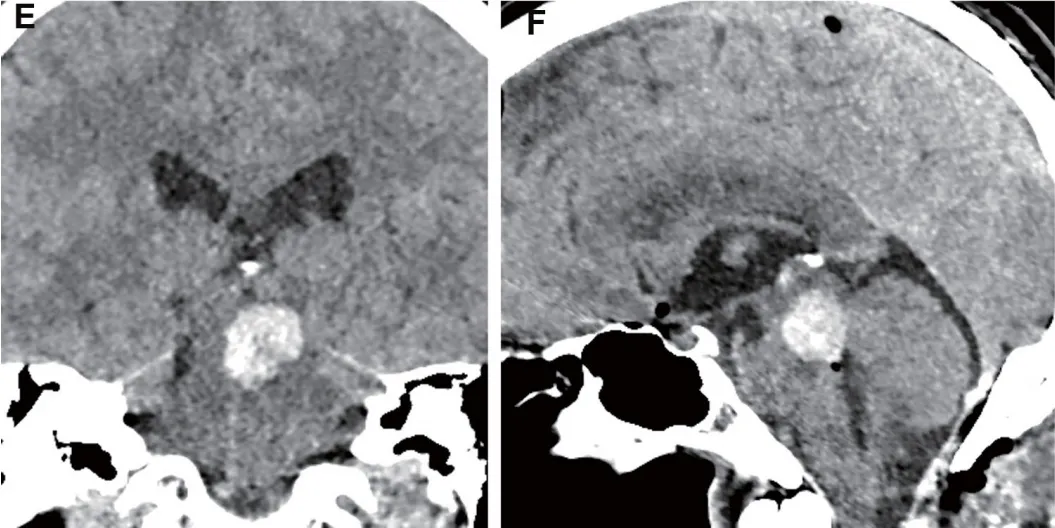

就在所有人以为手术成功、难关已过时,术后第一天,常规头部CT检查带来了令人担忧的发现:冠状位和矢状位重建图像清晰显示,切除腔内出现了新的血肿。这个血肿形成了占位效应,压迫周围的中脑结构。

这是中脑手术最凶险的并发症之一。手术团队当机立断:紧急二次手术清除血肿!医生再次通过原切口进入,快速找到出血点并止血,彻底清除血肿。

术后早期切除腔内的占位性血肿